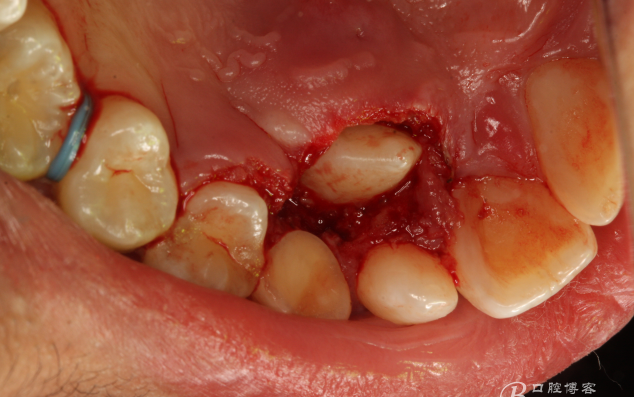

圖7.局部麻醉下、電刀切除覆蓋在13上的腭側(cè)粘膜組織。

圖8.繼續(xù)電刀切除腭側(cè)粘膜組織

圖9.清理切除部分腭側(cè)組織后的13牙冠。